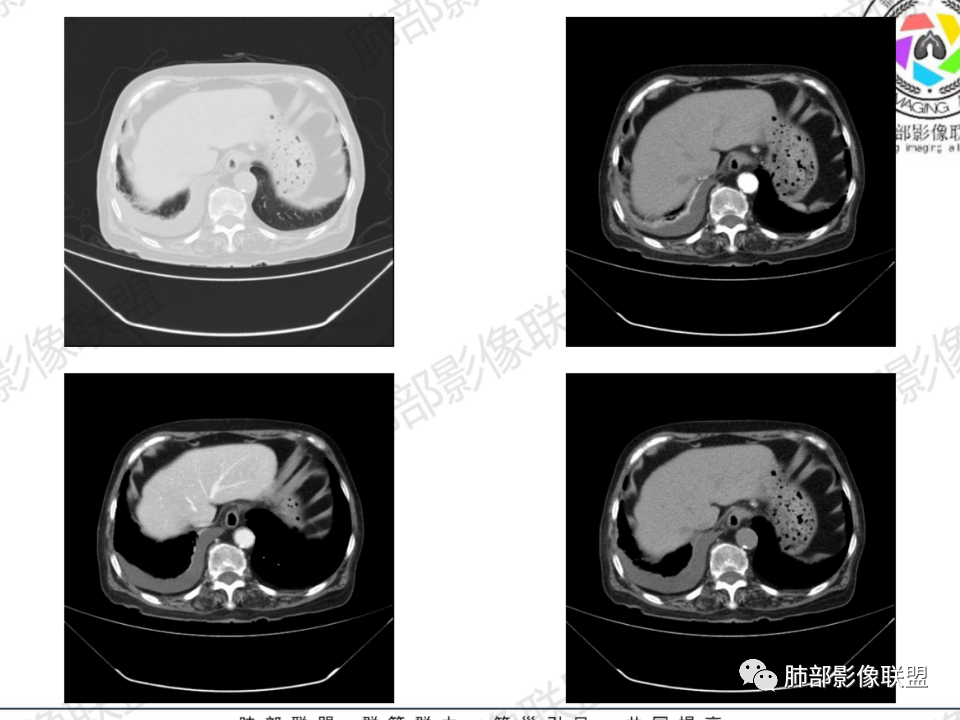

那个人:老年女性,亚急性病程,咳嗽发热。有垂体前叶功能减退,目前激素替代治疗,长期激素,量小,不知道累积量,没有目前激素水平指标。既往有淋巴结结核病史。肿瘤标记物Ca125升高。血沉升高,C反应蛋白轻度异常。影像,右肺上叶靠近肺门团块影,右肺门淋巴结钙化肿大,支气管狭窄,局部增厚,团块影外朝内改变,强化明显,血管破坏不明显,有粘液。和纵隔胸膜分界清楚,周围肺组织有斑片渗出影,右侧胸腔积液,考虑炎性?结核?支气管镜检查除外恶性飞鹰行动:老年患者,影像表现 右肺上叶占位性病变,边界清楚,有分叶征,内见细小钙化,右肺上叶支气管截断,增强病灶不均匀强化,病灶内有条状坏死区(扩张的支气管?),纵膈内未见增大淋巴结,考虑炎性病变,结核可能。一切∮随缘:右肺上叶实性肿块形态不规则,呈三角形,边缘分叶,边界伴有磨玻璃影,近段支气管未见明显显示,可能堵塞,病变平扫密度均匀,增强后可见低密度坏死无强化,周围略强化,右肺下叶散在结节。心包积液,及右侧胸腔积液,临床:有低热,低蛋白血症,肿瘤标记物高,考虑恶性:腺癌,神经内分泌癌(强化偏弱了),淋巴瘤,鉴别:结核红星:老年女性患者右肺上叶,肺门上区 分叶状肿块 ,右肺上叶支气管显示不清,增强扫描肿块,中等程度强化可见小斑片状坏死区,病灶内部可见斑点状钙化灶,病灶周围可见斑片状及小斑点状影,纵膈淋巴结增大,其他区域,胸膜下可见斑点状钙化。考虑肉芽肿性病变,结核的可能性大。老年患者最排除肿瘤性病变腺癌。土娃:右上肺不规则肿块影,边缘分叶,边界磨玻璃影欠清,病灶分叉状,内见点状钙化影及坏死灶,支气管堵塞,病灶增强强化不明显。考虑瘤样结核,鉴别淋巴瘤。张小兵:老年女性,亚急性病程,右肺上叶见不规则肿块,边缘平直凹陷为主,周围GGO边界不清,内见点状钙化及坏死灶,增强持续性渐进强化,右侧少量胸腔积液,双肺门及纵隔肿大淋巴结伴钙化,综合考虑慢性炎症。saf:老年患者,影像表现 右肺上叶占位性病变,边界清楚,有分叶征,增强病灶明显不均匀强化,纵膈内未见增大淋巴结,考虑炎性病变,结核可能。小兜:老年女性,咳嗽喘息一月,发热三天,肿瘤标志物升高,长期激素替代治疗。CT示右肺上叶近肺门不规则实变影,周围伴磨玻璃影,增强持续性渐进强化,内部血管破坏不厉害,内部可见多发条形低密度灶,右侧胸腔可见少量积液,双肺门及纵隔可见钙化淋巴结,考虑为炎性病变,结核可能玫:女,79咳嗽,喘息一月,发热三天入院,右肺上叶不规则形软组织密度肿块影,边界清晰,边缘见分叶及细短毛刺,病灶内见点状钙化影及稍低密度区,病灶边缘呈磨玻璃样改变,增强扫描,病灶呈不均匀性强化,考虑炎性病变,鉴别鳞癌。大雄:老年女性,既往诊断淋巴结结核,提示已治愈,近2年服用激素,诱导结核复燃→发热;纵隔肺门淋巴结肿大钙化,压迫支气管,右肺上中下叶支气管均狭窄→喘息咳嗽;尖段支气管受累闭塞→肺不张、支气管粘液栓;累及胸膜,结核性胸膜炎并胸水→右侧胸痛;实验室,血沉快,CA125高,低蛋白,符合;下一步,支气管镜尖段支气管刷检抗酸染色周太狼:老年女性,亚急性病程,肿瘤标志物升高。CT示右肺上叶尖段不规则肿块影,有分叶、收缩,周围伴磨玻璃影,增强渐进强化,内部可见多发条形低密度灶,右侧胸腔及心包少量积液,纵隔内淋巴结稍增大。倾向于恶性病变,肺癌伴阻塞性炎变可能。丽:老年女性,右肺上叶不规则软组织肿块,边缘清晰,内密度不均,可见点状钙化及粘液栓,周围可见片状高密度影,增强后均匀强化,内多发低密度,纵膈多发钙化淋巴结,考虑结核可能大,建议结合支气管镜检查除外肿瘤宇宙:右胸廓缩小,右肺上叶团块影及不张,平直边,周围磨玻璃影,纤细胸膜牵拉,上叶尖段支气管堵塞,明显延迟强化,可见支气管粘液栓,两肺门钙化淋巴结,右侧胸水,考性炎性肉芽肿,鉴别腺癌王秀仙:右肺上叶肺门区肿块,上叶支气管开口阻塞,形态不规则,密度不均,内可见支气管粘液栓及多发小灶性坏死,周围磨玻璃影边缘模糊,渐进强化,右侧胸腔积液、胸膜钙化,考虑炎性肉芽肿性病变,慢性炎症。鉴别鳞癌,结核。刘丹:老年女性,右肺上叶肿块伴钙化,右肺上叶支气管截断,增强后均匀强化,周边可见点片状模糊影,右侧胸腔积液,右肺门淋巴结增大,考虑占位并阻塞性炎症,肿瘤?结核?建议纤支镜检查。小飞:右肺上叶纵隔旁软组织肿块,边缘深分叶、长毛刺及毛刷样短毛刺,边缘磨玻璃影,磨玻璃边界模糊,支气管截断,平扫密度不均,可见点状钙化,增强不均匀明显强化,心影增大,心包积液,右侧胸腔积液,考虑恶性肿瘤,腺癌?秦化君:右肺上叶不规则分叶软组织密度肿块,边缘清晰,胸膜牵拉,周围花花草草,上叶尖段支气管阻塞,内可见点状钙化,增强后密度不均可见支气管粘液栓及坏死区,内见血管分枝。中间段及中叶,下叶支气管狭窄,壁见钙化。右肺门淋巴结肿大,右侧胸腔积液,心包粘连肥厚。考虑1右上肺恶性病变,鳞癌?2右肺多叶段支气管狭窄,考虑支气管内膜结核?3胸腔积液及肺门淋巴结肿大,转移?风儿:老年女性,右肺上叶肿块,形态不规则,外围大内带小,边缘分叶膨隆平直及毛糙,密度不均,内见支气管粘液栓及多发小灶性坏死,坏死边缘清晰 ,渐进强化,上叶尖段支气管阻塞,叶支气管壁有局限性增厚,邻近胸膜腔微积液;纵隔及双肺门淋巴结肿大,部分钙化,右侧胸腔积液、心包积液、胸膜钙化,考虑炎性,肉芽肿性结核可能性大。鉴别鳞癌,女性及血供均不支持;腺癌,坏死边界太清晰。流心明智:老年女性,79岁,咳嗽、气短1月,发热3天。胸CT:右肺上叶见不规则肿块,边缘有膨隆、有平直凹陷,周围GGO边界不清,病灶内见点状钙化、粘液栓,尖段支气管未见,增强持续性渐进强化,右侧少量胸腔积液,双肺门及纵隔肿大淋巴结伴钙化,肺动脉增粗。考虑:右上叶尖段堵塞并慢性炎症,支气管TB并结石?鉴别Ca

临床信息:老年女性,亚急性病程,咳嗽发热。有激素使用史。既往有淋巴结结核病史。肿瘤标记物Ca125升高。血沉升高,C反应蛋白轻度异常。 影像所见:右侧胸廓相对狭小,右肺上叶不规则团块影贴附纵隔旁,轻度分叶,整体密度较均匀,偶见钙点。

相应上叶尖端及前段支气管开口未能追踪(阻塞),开口处见钙化。病灶渐进性强化,并衬托出较完整尖段及前段含液支气管影。支气管开口区域未见异常高密度强化(如类癌等)及相对乏血供区(如鳞癌)。病灶区未见液化坏死。右上纵隔及胸廓入口区未见病灶胸膜外突破(栽赃)。

右肺上叶后段等区域散在片状影,边界不清(提示渗出性病灶)。

纵隔及双肺门见钙化淋巴结。心包积液,右侧胸腔积液(提示存在活动新病灶)。双侧胸膜下见多发斑点状钙化,胸廓变形(提示存在结核基础病变可能)。 诊断意见:综上,右肺上叶块状影更符合继发性肺结核。 最后小结:既往诊断淋巴结结核,提示已治愈。近2年服用激素,可疑诱导结核复燃,也可引起发热。纵隔肺门淋巴结肿大钙化,压迫支气管,右肺上中下叶支气管均狭窄,所以引起喘息咳嗽。尖段支气管受累闭塞,导致肺不张、支气管粘液栓,出现条状无强化区。病变累及胸膜,导致结核性胸膜炎并胸水,引起右侧胸痛。实验室检查血沉快,CA125高,低蛋白,均符合结核。下一步,建议支气管镜尖段支气管刷检并抗酸染色。(本段摘自於雄老师精彩发言)